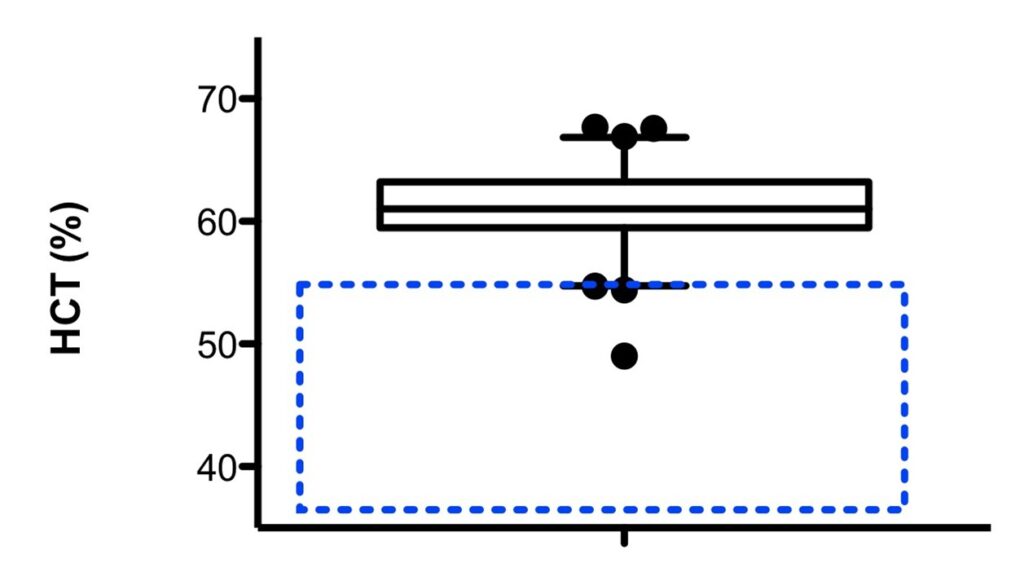

Greyhounds and several other sighthound breeds have hematology (blood cells) and blood chemistry values different from those in most dog breeds. For example, their red blood cell counts are higher, and their platelet and white blood cell counts lower. Some of their kidney values (mainly creatinine and SDMA) are also high. IDEXX laboratories in the US now uses “Greyhound specific” reference intervals (RIs) when reporting values. As an example, below is a graphic of the hematocrit (HCT) or red cell mass in Greyhounds (box) compared with the normal values for dogs (dotted blue box).